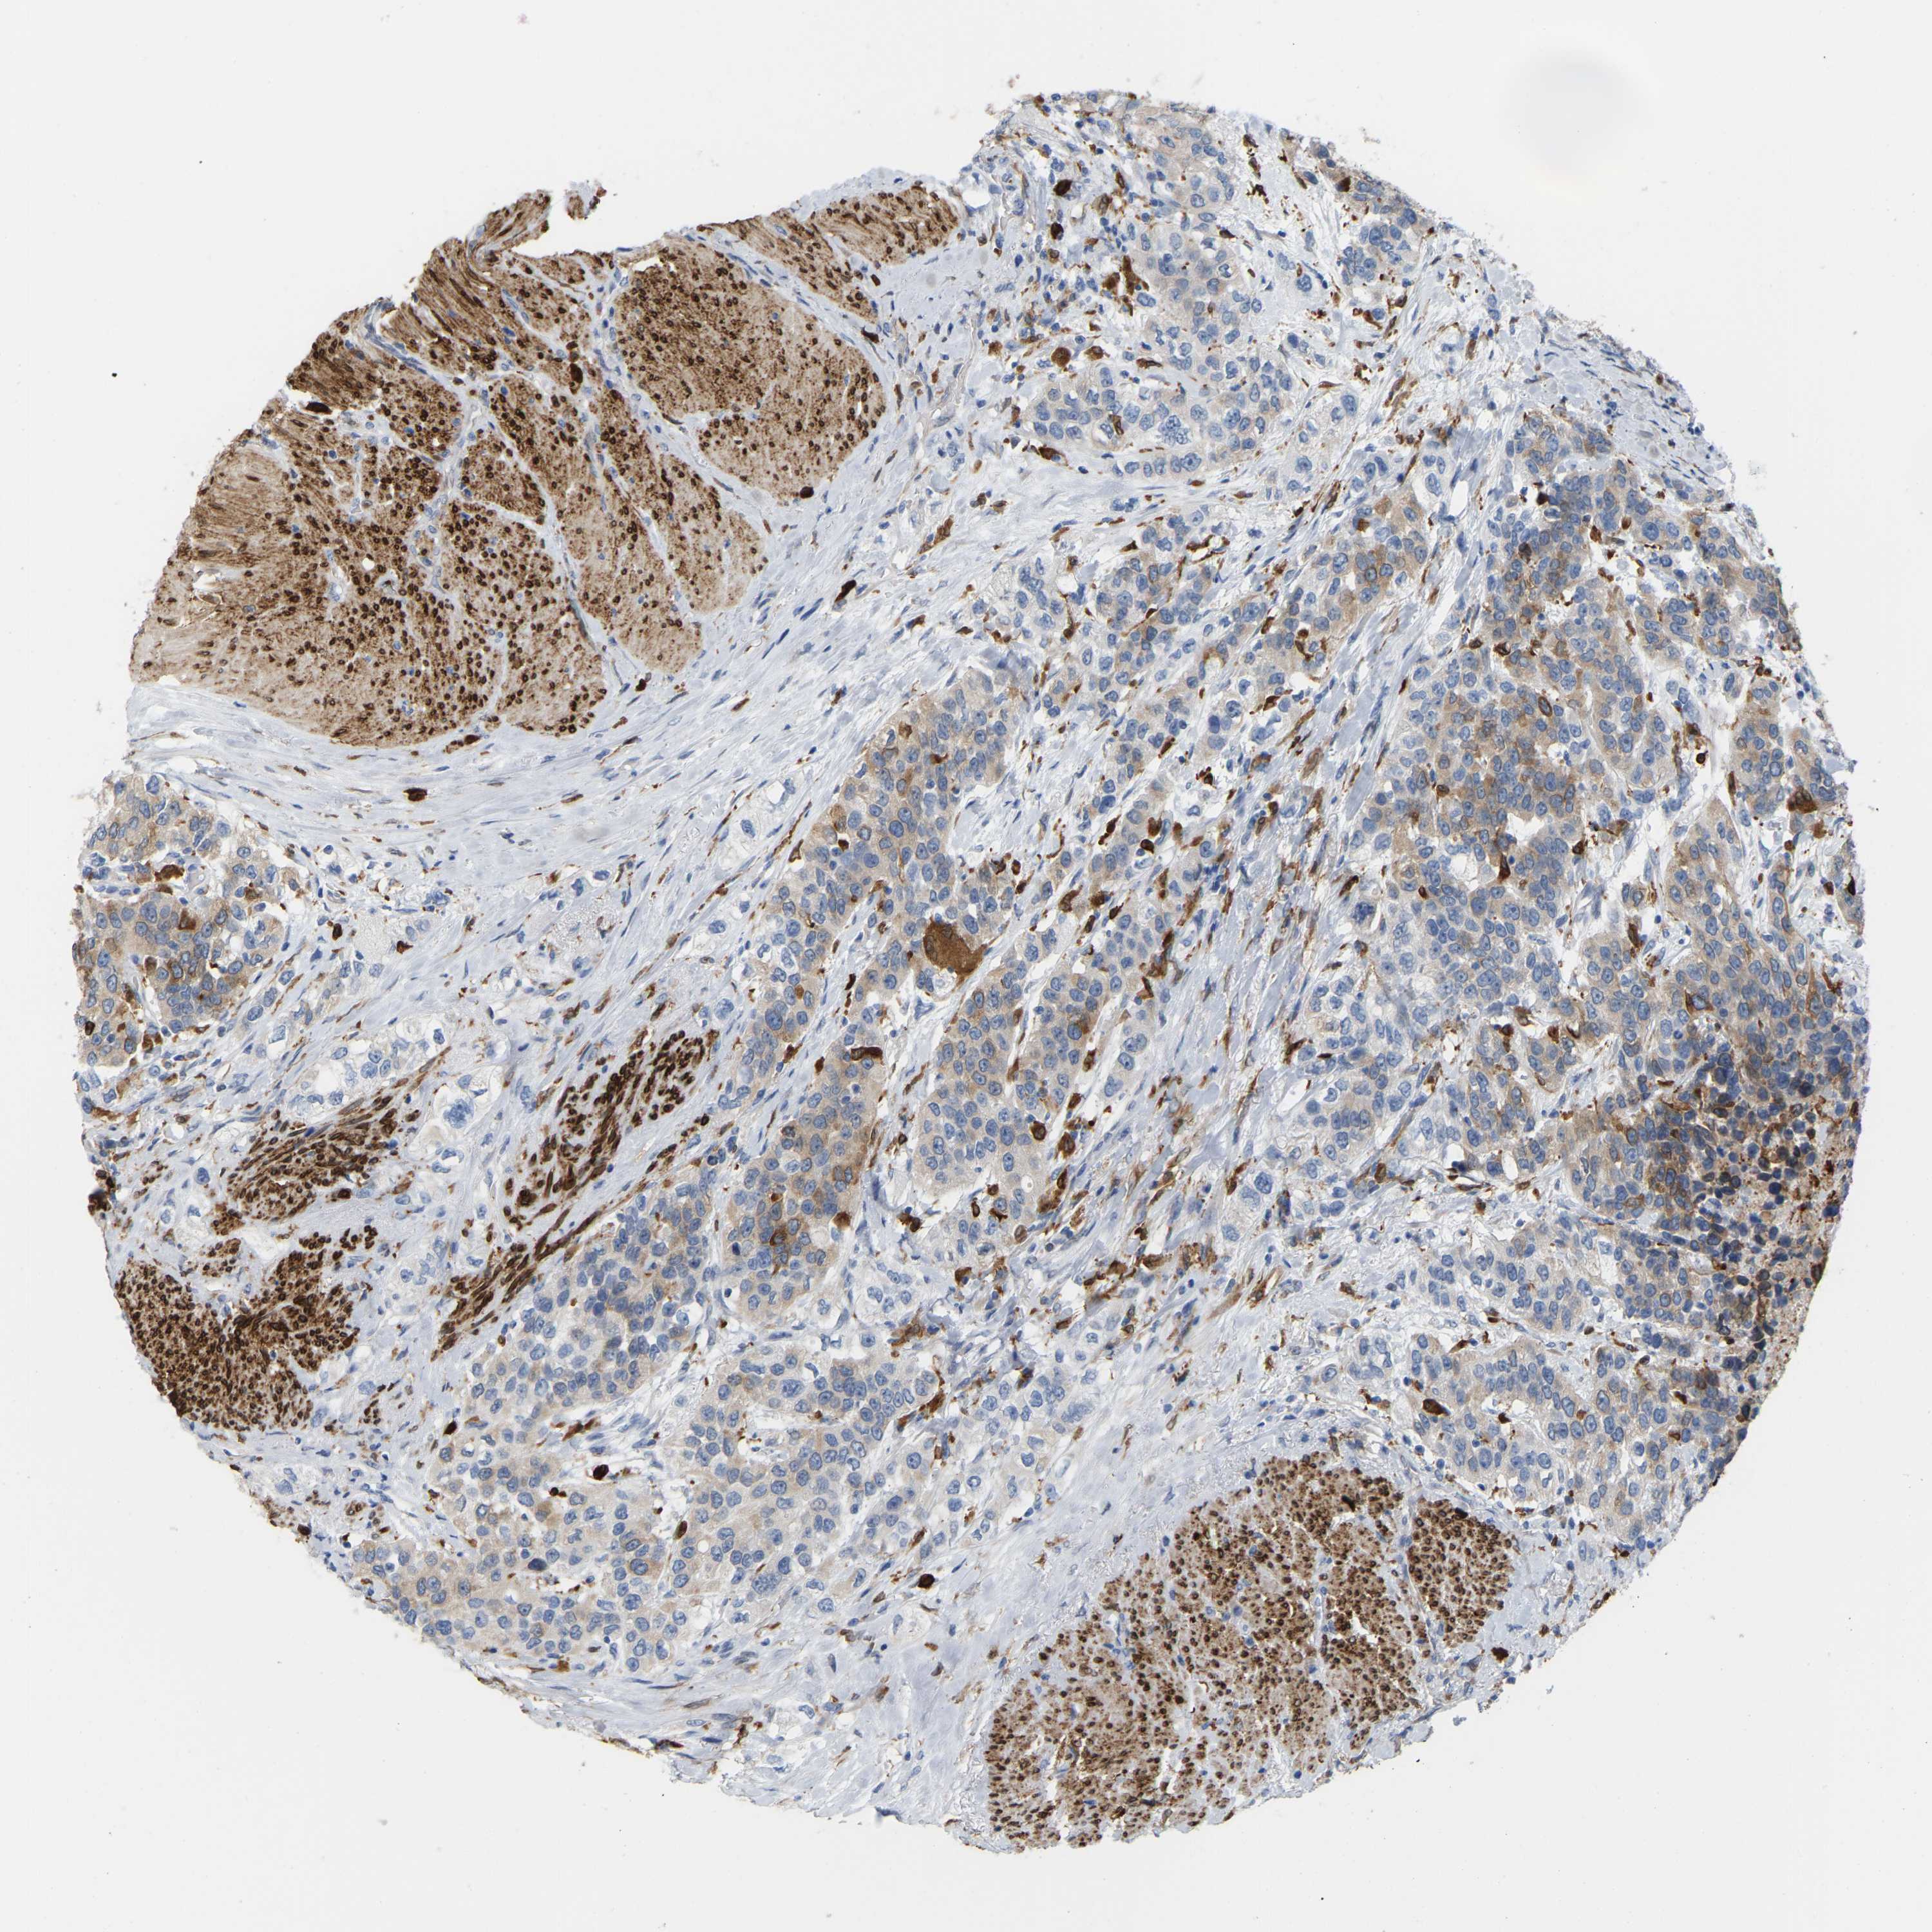

UROTHELIAL CANCER - Protein expressioni

A mouse-over function shows sample information and annotation data. Click on an image to view it in a full screen mode. Samples can be filtered based on level of antibody staining by selecting one or several of the following categories: high, medium, low and not detected. The assay and annotation is described here.

Note that samples used for immunohistochemistry by the Human Protein Atlas do not correspond to samples in the TCGA dataset.

Antibody stainingi

Antibody staining in the annotated cell types in the current human tissue is reported as not detected, low, medium, or high, based on conventional immunohistochemistry profiling in selected tissues. This score is based on the combination of the staining intensity and fraction of stained cells.

Each image is clickable and will lead to virtual microscopy that enables deeper exploration of all samples and also displays staining intensity scores, fraction scores and subcellular localization as well as patient and tissue information for each sample.

Antibody HPA002834

Antibody CAB020315

Staining

High

Medium

Low

Not detected

Intensity

Strong

Moderate

Weak

Negative

Quantity

>75%

75%-25%

<25%

None

Location

Nuclear

Cytoplasmic/membranous

Cytoplasmic/membranous,nuclear

Urothelial carcinoma, High grade

Urothelial carcinoma, Low grade

Adenocarcinoma, NOS